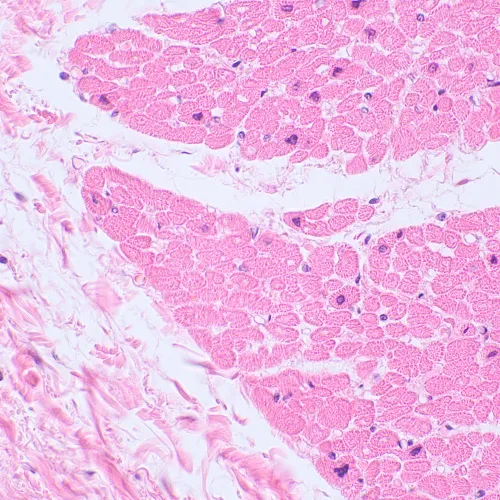

Фотографии в высоком качестве (zip)